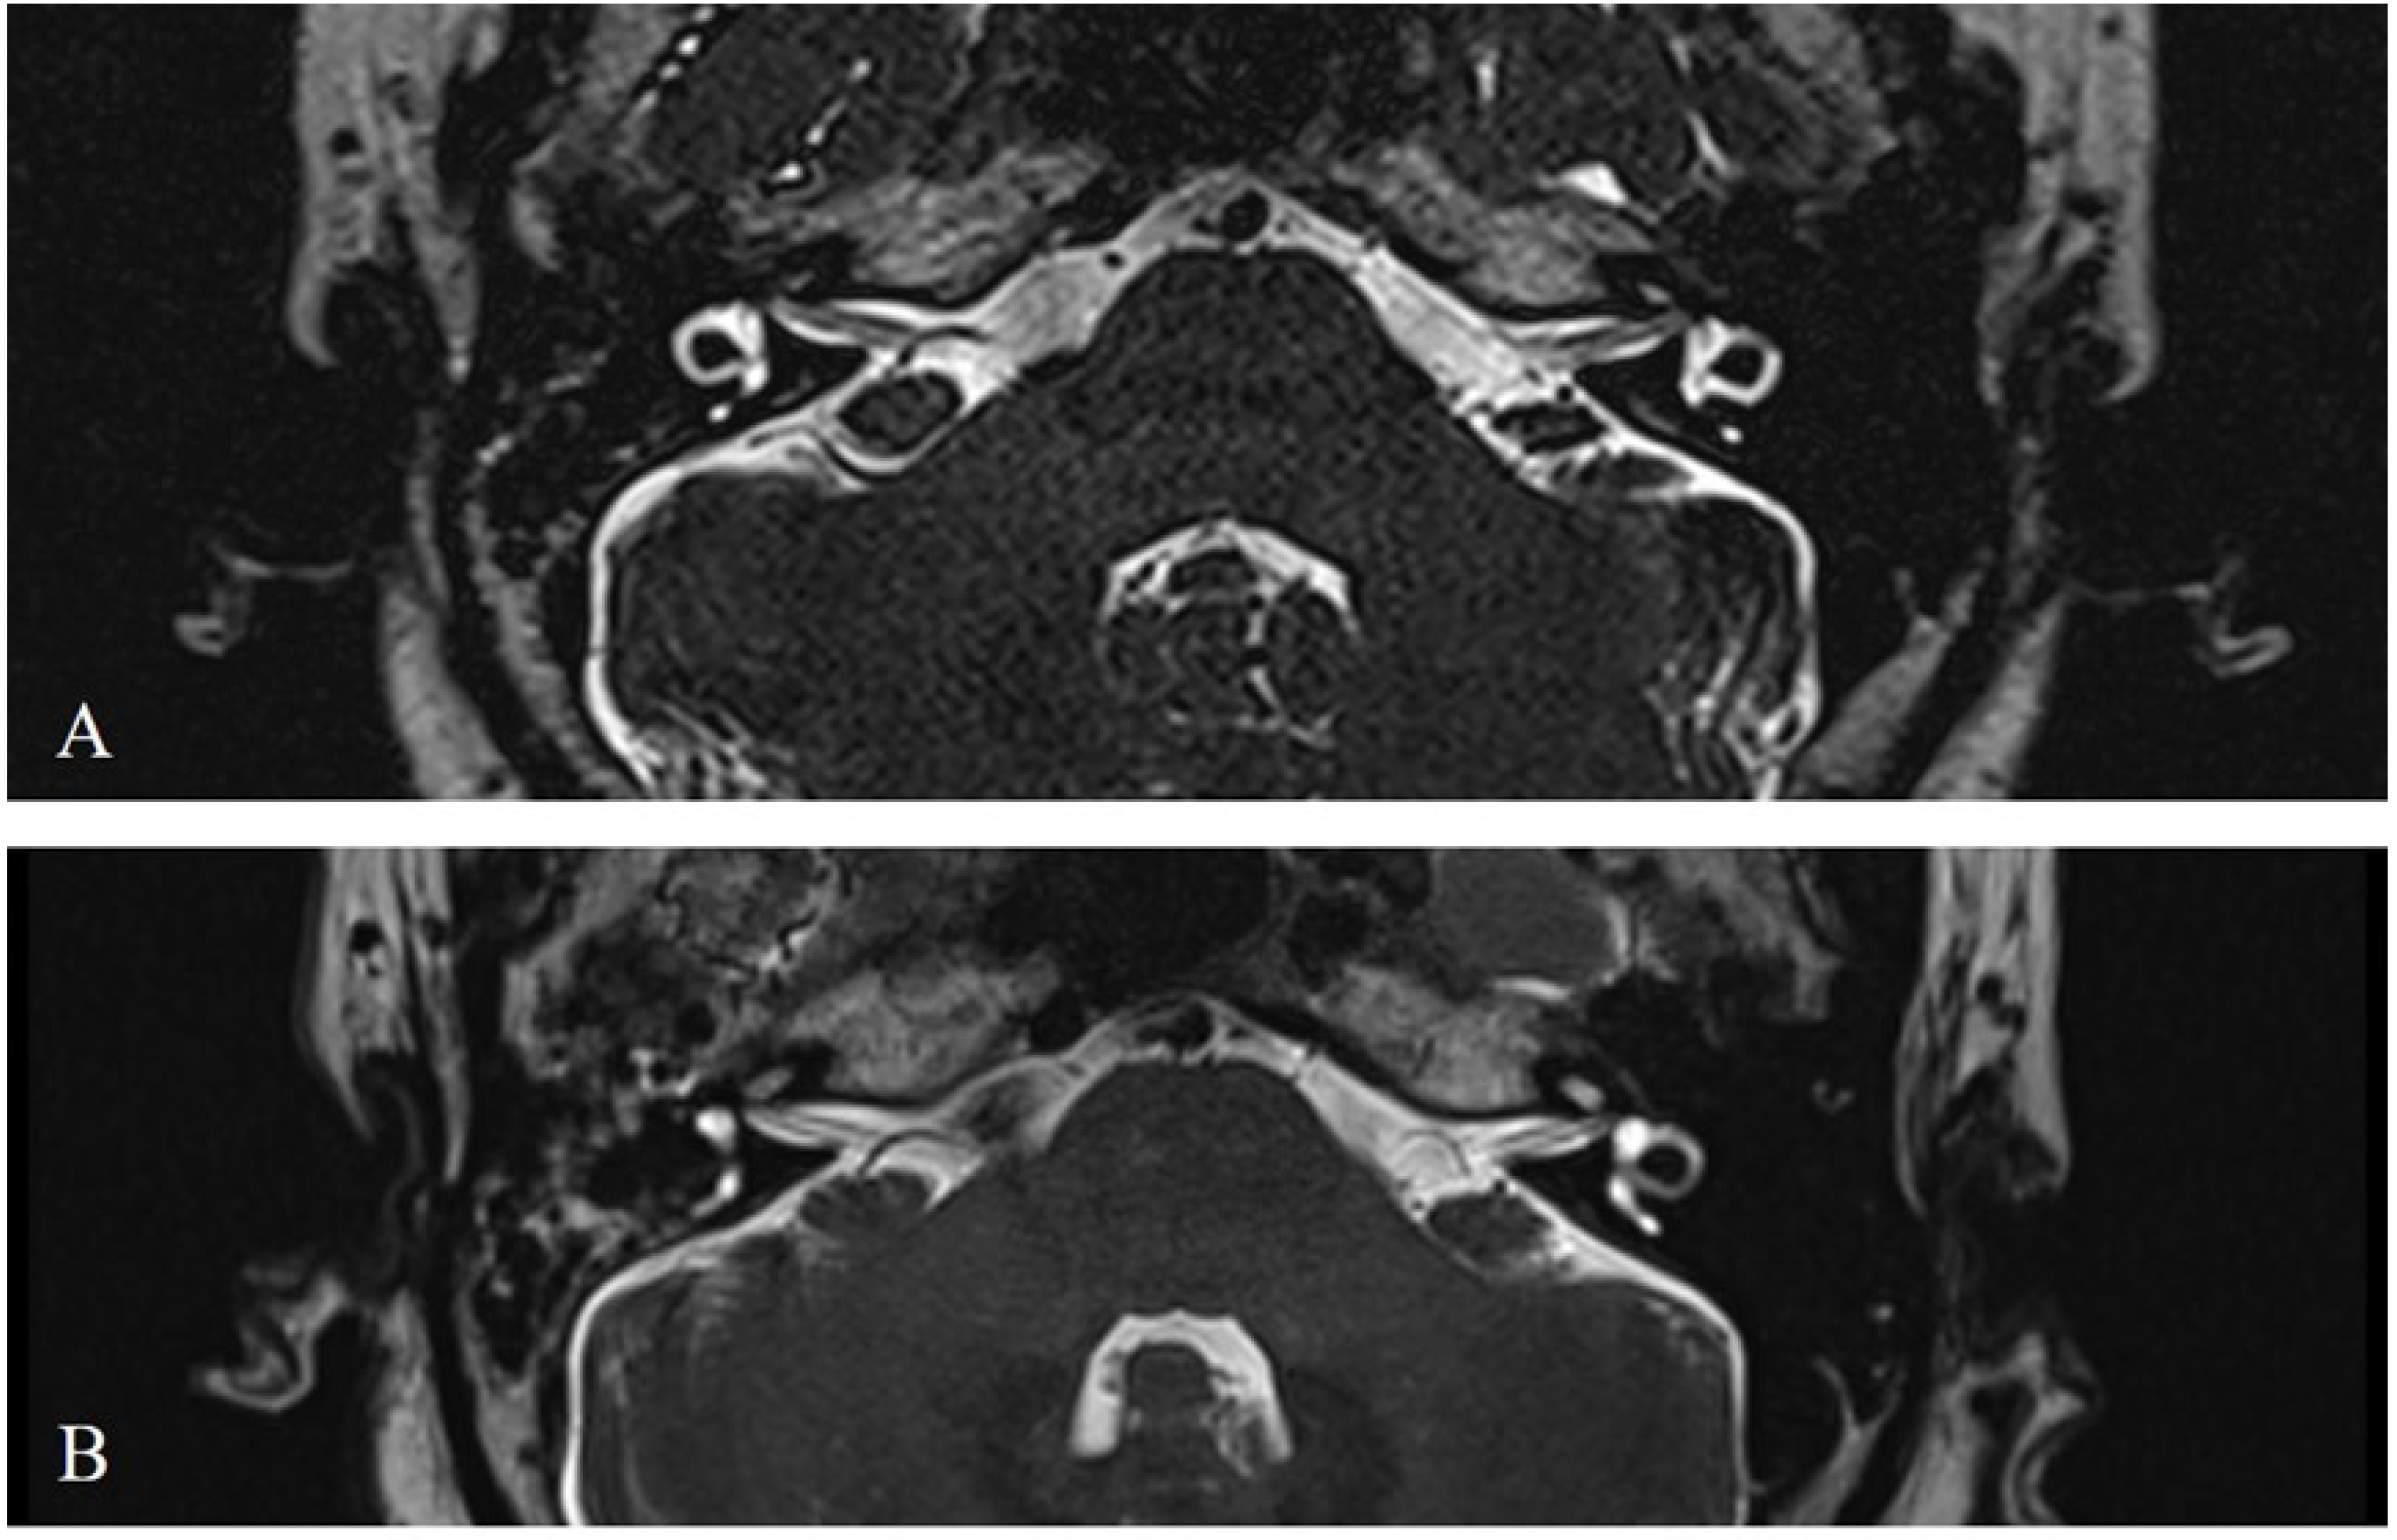

- Wang, E.; Liu, B.; Wang, Y.; Yao, W.; Sun, Y. , Occlusion of the Lateral Semicircular Canal Through the External Ear Canal: A Case Report. Ear Nose Throat J 2022, 101, NP447–NP450. [Google Scholar] [CrossRef]